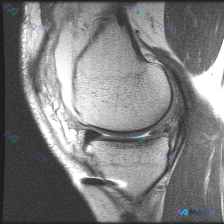

刚看到这个膝关节MRI读片的病例,整理一下完整的病例信息和分析思路,和大家讨论一下这种情况的处理。 病例基础信息 本次提供的是单幅膝关节矢状位T1加权MRI影像,核心疑问是评估是否存在半月板异常。 影像学观察结果 我们先按解剖结构整理观察结果: 1. 骨骼结构:股骨远端、胫骨近端、髌骨骨皮质连续,骨...

看到一个很有代表性的读片病例,怀疑半月板异常但单张T1加权MRI没有发现明确问题,整理了分析思路和大家分享。 病例核心信息 问题:临床怀疑半月板异常,提供单张膝关节矢状位T1加权MRI,需要做影像观察和分析 影像系统性观察结果 1. 骨性结构:股骨远端、胫骨近端、髌骨轮廓规整,骨髓信号正常,未见骨质...

今天看到一份很有代表性的读片病例,整理出来和大家分享一下,核心问题就是:临床怀疑半月板异常,但是只给了一张膝关节矢状位T1加权MRI,阅片没发现明确异常,这个情况该怎么分析? 先整理一下这份影像资料的基本信息 这是单张膝关节正中矢状位T1加权像,图像质量清晰,没有运动伪影,能看到股骨远端、胫骨近端、...

最近碰到一个有意思的读片病例,患者临床提示半月板异常,但提供的单张MRI并没有看到明确问题,整理一下完整的分析思路给大家参考。 一、病例核心信息 这是一份膝关节矢状位MRI扫描图像,临床问题是排查"半月板异常",我们先对影像做系统性评估: 1. 影像基本信息:这是T2/质子密度加权矢状位图像,清晰显...